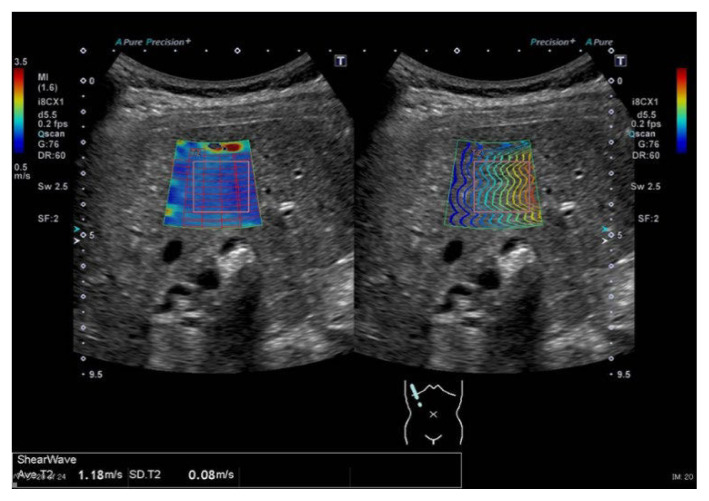

SWE imaging was performed in all patients in the outpatient ultrasonography room. SWE measurements were performed using an Aplio-500 or Aplio-i800 device and a 375BT probe (Canon Medical Systems, Tokyo, Japan). During the examination, the patients were placed in the supine position. The tip of the transducer probe was placed between the ribs over the right lobe of the liver. The detection site was fixed 1.0 to 2.0 cm beneath the surface of the right liver, away from the intrahepatic vessels. Three successful acquisitions at different locations were obtained for each patient, the mean value was calculated, and the results were expressed as shear wave propagation velocity (m/s) (Figure 1).